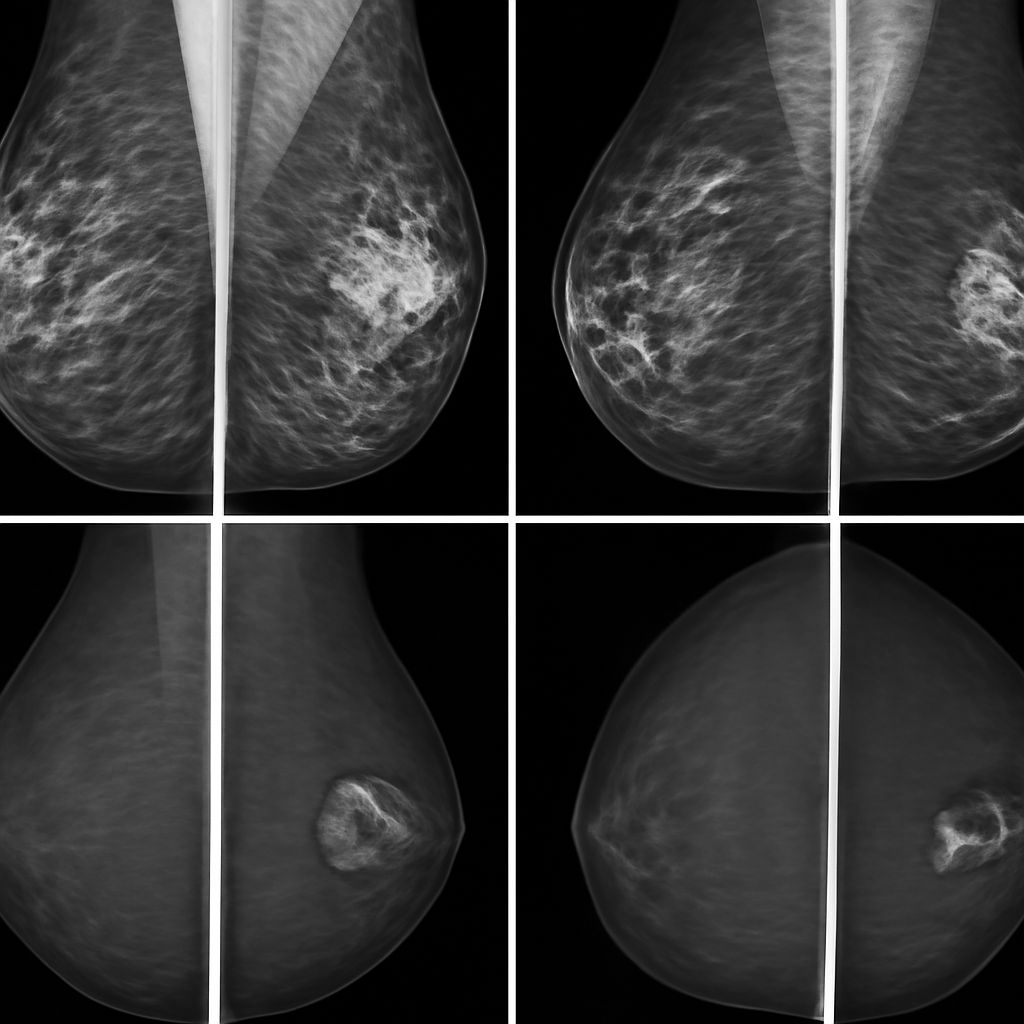

Breast MRI is typically ordered for high-risk screening in women with BRCA1 or BRCA2 mutations, strong family history, or prior chest radiation. It’s also used as a staging tool when breast cancer is already diagnosed, to determine tumor size and check for additional sites of disease. MRI of the breast is frequently used to evaluate implant integrity when silicone rupture is suspected, as it’s more accurate than ultrasound for this specific application.

What Breast MRI Detects

An MRI of the breast uses contrast dye (gadolinium) to evaluate blood flow patterns in breast tissue. Cancer tends to enhance quickly due to its blood supply characteristics, which shows up distinctly on MRI sequences. The scan also evaluates lymph nodes in the axilla, chest wall involvement, and skin changes. For implant evaluation, specific sequences without contrast detect silicone outside the implant shell, which indicates rupture.

If your breast MRI shows a finding that requires tissue sampling, you’ll likely be scheduled for an MRI-guided breast biopsy. The breast biopsy CPT code used for MRI-guided core needle biopsy is different from ultrasound-guided or stereotactic procedures, and the billing reflects the higher complexity and longer procedure time of MRI guidance. Your facility should be able to tell you the expected CPT code and what cost-sharing applies before you schedule the biopsy.